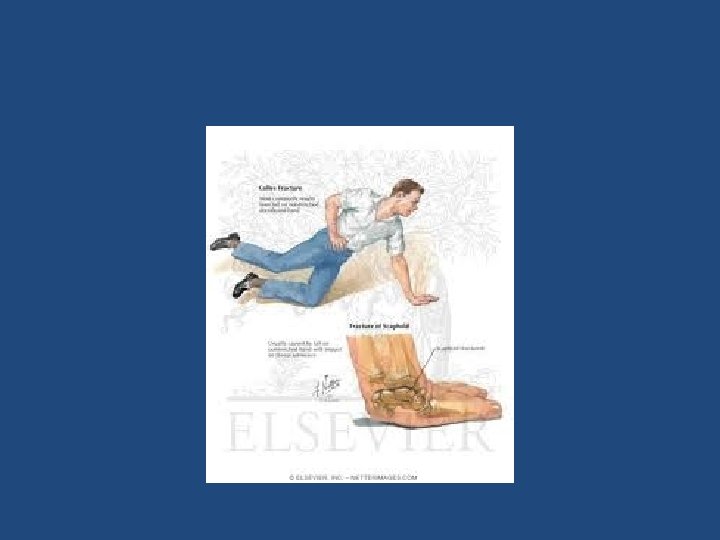

DISTAL RADIUS FRACTURE • Most common fracture of upper extremity. • Most frequently are seen in older women. • Young adults fractures are most commonly secondary to high energy trauma.

• Extra-articular: – Colles’ Fracture: dorsal angulation, shortening and radial deviation – Smith’s fracture: shortening and volar angulation. (reverse Colles’) • Intra-articular: – Barton’s fracture: volar or dorsal – others